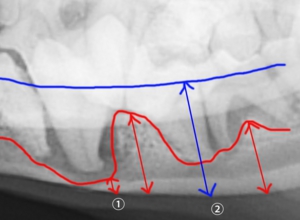

*下の画像をご覧ください。青の矢印(②)で描写された幅が本来の下顎の幅です。つまり歯周病がなければ歯(M1)と下顎骨が一緒になって下顎の幅と考えられるわけです。しかし歯周病によって赤の矢印の幅分まで下顎が薄くなっております。特に①などに関しては骨折のリスクがあると考えてよいでしょう。